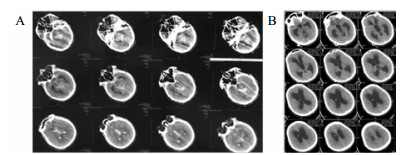

1 资料与方法病例1, 女,24岁,2015年12月以“脑干出血破入脑室术后1年,脑积水V-P分流术后”入院。入院时为植物状态,GCS 8分,双瞳孔3.0 mm, 对光反应灵敏,双侧巴氏征阳性;V-P分流调压阀压力为1.0(Medtronic, Minnesota, USA),储液囊外接引流管,压力为外耳道连线上方10 cmH2O (1 cnH2O = 0.098 kPa)。诊断为:脑干出血术后、脑积水、永久性植物状态(图 1)。

| A:2014年12月2日CT;B: 2015年12月8日入院CT,分流压力为1.0 图 1 病例1 CT |